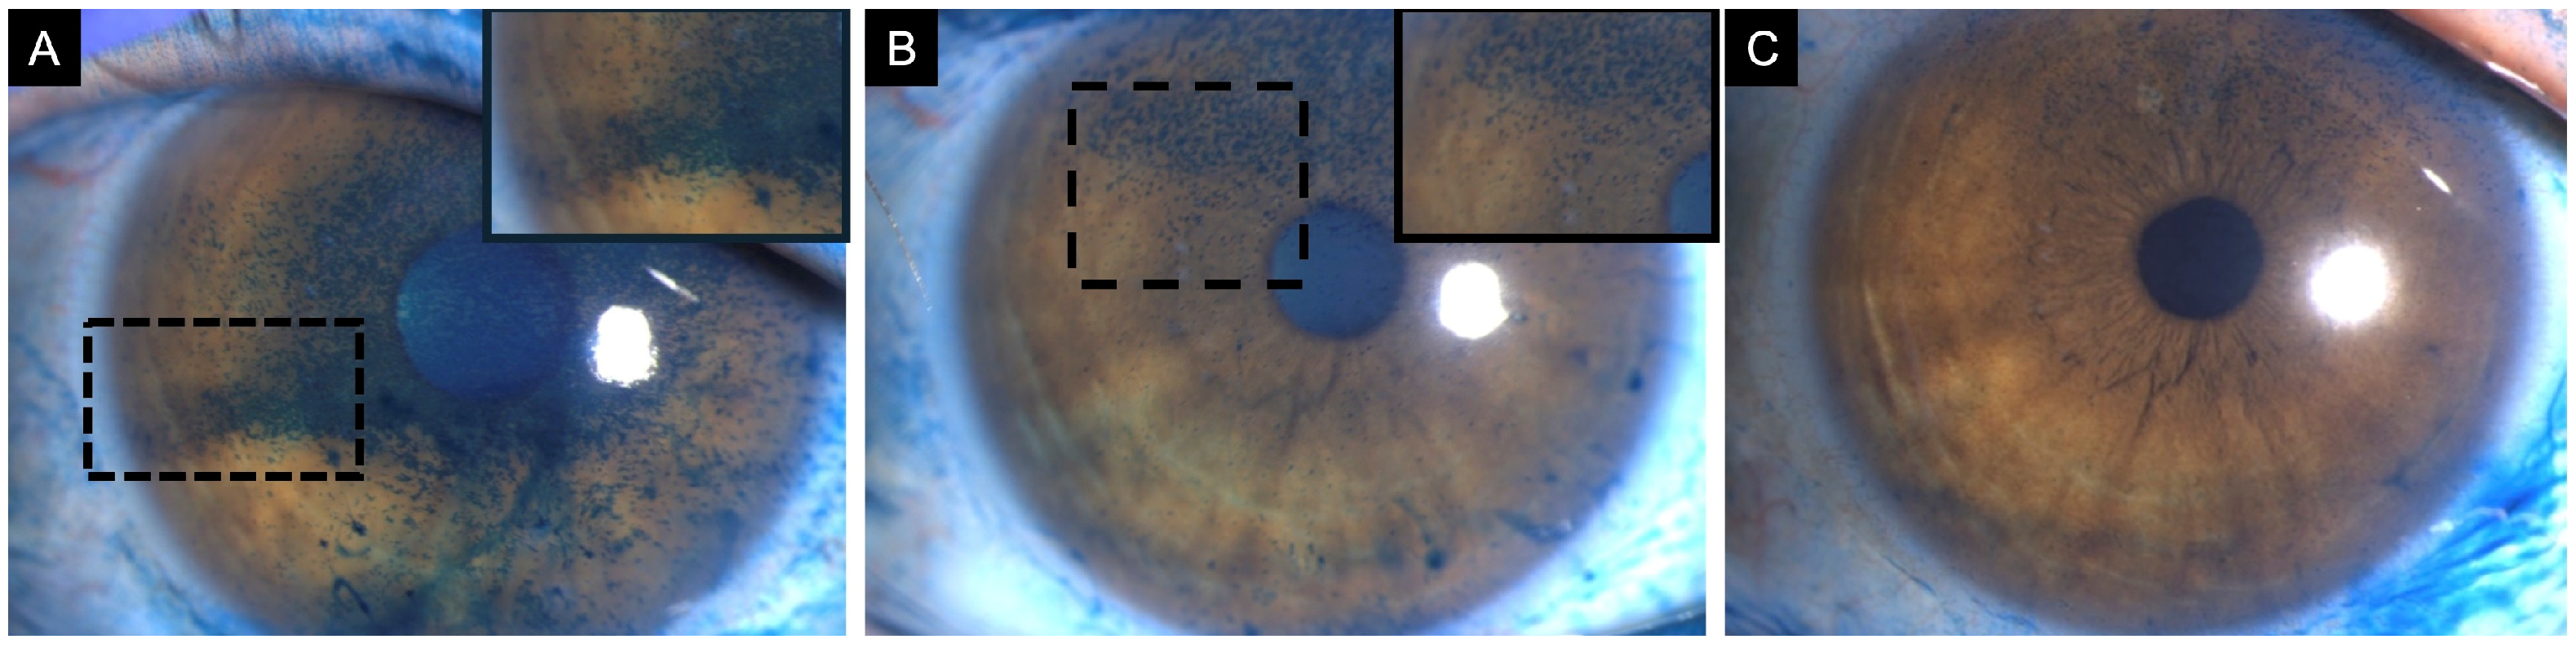

Non-invasive techniques for measuring the optical quality of the air-tear film interface include the double-pass method, videokeratoscopy, retroillumination, wavefront aberrometry, and interferometry. Detailed description of each of these processes can be found in other sources [26]. Tear film instability leads to increased HOAs and ocular light scattering, which results in vision fluctuations during blinking and glare, respectively [27]. Koh et al. analyzed the sequential changes in HOAs after blinking in patients with DED both with and without central superficial punctate keratopathy (SPK) using a wavefront sensor [28]. They found that DED patients with central SPK exhibited significantly higher coma-like, spherical-like, and total HOAs compared with those without central SPK. Sequential post-blink measurements were consistently higher in eyes with DED and central SPK. In contrast, eyes without central SPK demonstrated consistently lower total HOAs that resembled the patterns found in healthy eyes [28]. Therefore, it is crucial to consider not only a diagnosis of DED but also the presence of irregular epithelial surface in the optical zone (Figure 1).

Corneal sensitivity serves as a surrogate marker for the health of the ocular surface. Corneal nerves regulate the blinking and tearing reflexes, transmit sensation, and modulate wound healing [74]. Corneal sensitivity can be assessed with a cotton wisp, the Cochet-Bonnet esthesiometer, and with the recently approved Brill non-contact esthesiometer [75,76]. Lyne reported that 29 of 29 eyes (100%) had almost complete anesthesia in the superior half of the cornea one year after extracapsular cataract extraction (ECCE), with only 3 (10%) recovering normal sensitivity two years after [77]. In otherwise healthy eyes, complete recovery of corneal sensitivity has been observed three months following phacoemulsification surgery [78]. However, in patients with pre-existing OSD, disruption of corneal nerves during cataract surgery may lead to increased epithelial permeability and reduced wound healing, which can be assessed with in-vivo confocal microscopy (Figure 4) [78,79].